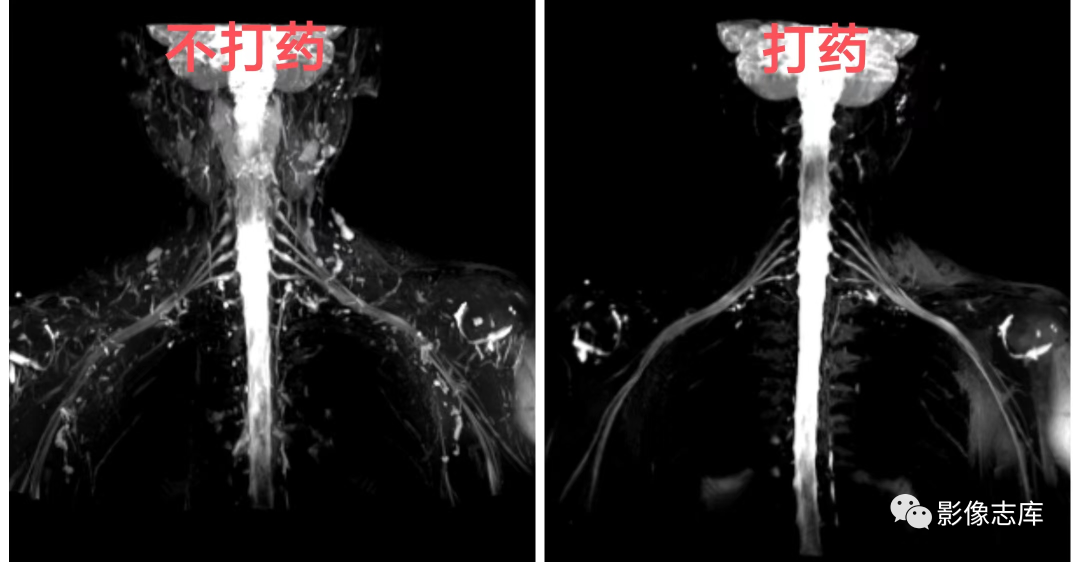

不打药和打药区别:利用重T2结合脂肪抑制STIR序列,可达到一定背景组织抑制的目的,但是血管和淋巴结很难将其抑制,为了达到这些组织不被显现,因此引入打药后的T2负性增强原理,由于微小血管和淋巴结可吸收少量对比剂,对比剂可缩短T2弛豫时间,因此通过打药后的T2加权可达到微小血管和淋巴结抑制的目的。